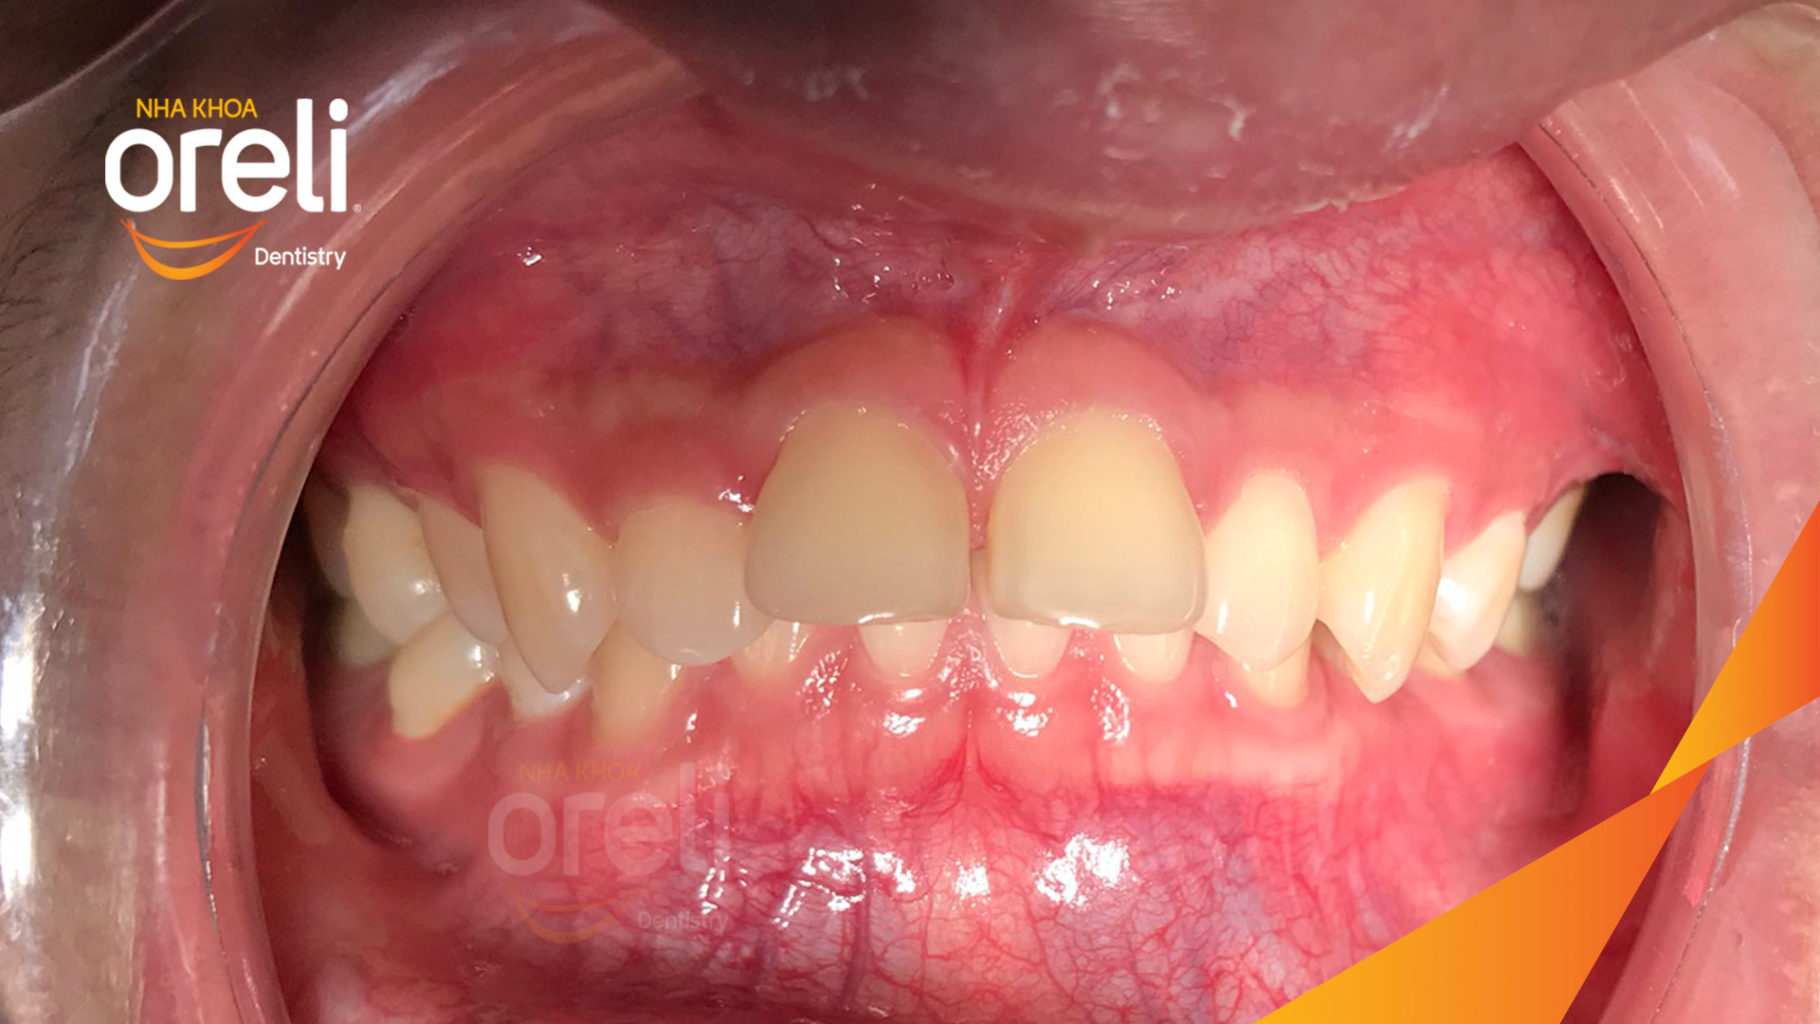

Giải pháp: làm đều chỉnh khớp cắn sâu không nhổ răng

Kết quả: khớp cắn đúng, cằm tiến ra trước với mặt nghiêng đẹp

Hình ảnh thực tế